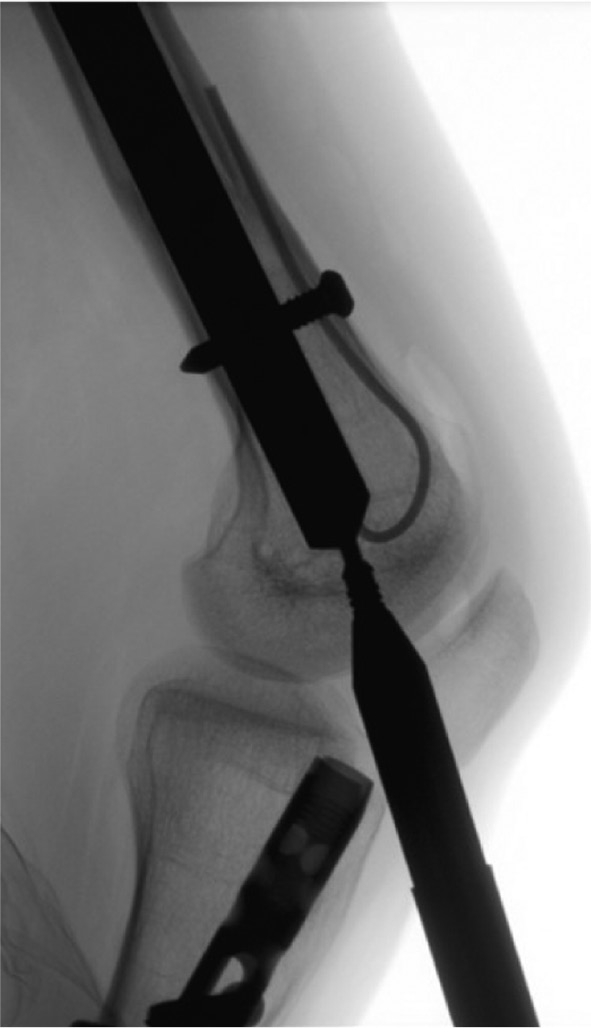

Figure 4. Rotate the limb until the distal interlocking elements are in perfect profile. This will help determine if there has been any bone growth over the top of the fixation elements that might preclude a percutaneous removal attempt. It is additionally advised to use this position to remove the screw. Placing the screwdriver in-line with the screw in perfect profile and perpendicular to the fluoroscopy beam will ensure proper orientation and facilitate engagement into the screw head.

jposna20220031_fig4.jpg